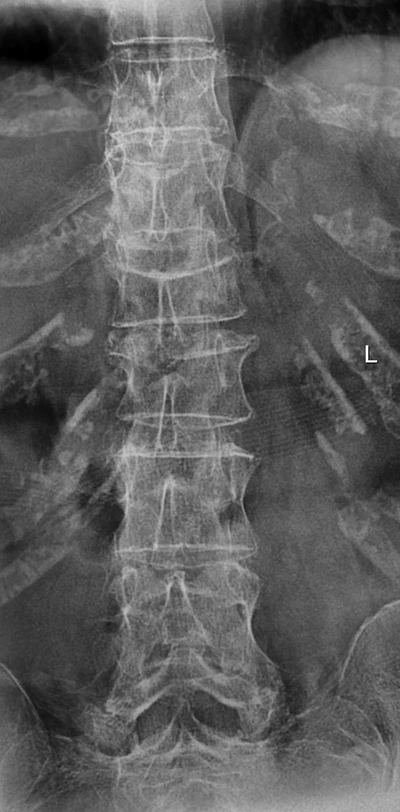

raggi colonna vertebrale